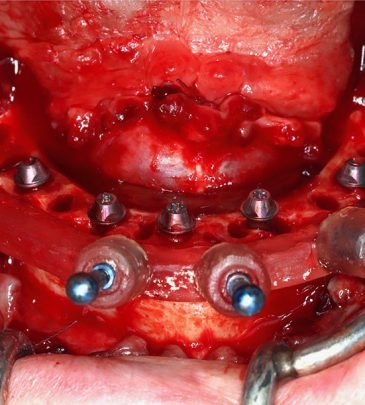

Our team of reputed dental practitioners is committed to ensuring that our courses are relevant, engaging, and reflect the latest advances in dentistry. Our wealth of clinical experience is leveraged through the collaborative effort in teaching fundamental concepts to advanced procedures in restorative dentistry, implantology, orthodontics, and periodontics.